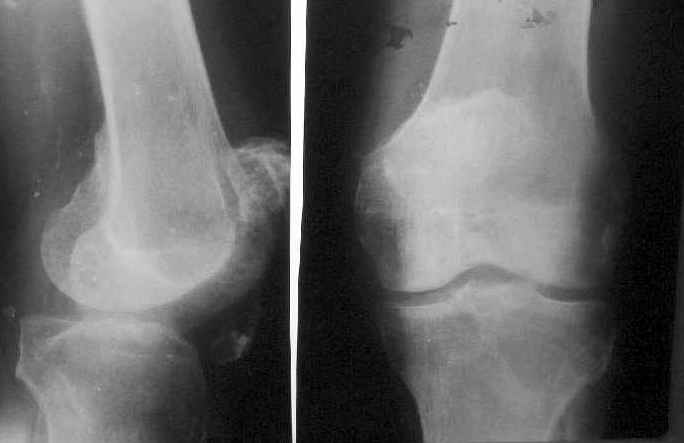

Пациент 53 лет травма 25.11.02. в салоне автомашины, получил множественные переломы ребер с ушибом легких и гемопневмотораксом, ротационно нестабильное повреждение таза: перелом боковых масс крестца, разрыв лонного сочленения, оскольчатый поперечный юкстатектальный перелом левой вертлужной впадины с центральным вывихом бедра и сегментарным переломом головки, перелом крыла правой подвздошной кости. Открытый многооскольчатый перелом костей правого предплечья, перелом правого бедра в нижней трети, перелом надколенника слева, перелом лодыжек левой голени с переломом заднего края левой большеберцовой кости подвывмхом стопы.Бедро срослось на вытяжении, лодыжки в гипсе, предплечье в аппарате. Под наше наблюдение попал 25.03.03. Выполнен чрескостный остеосинтез таза, с постепенной коррекцией положения отломков, затем 28.04.03 реконструкция вертлужной впадины для эндопротеза, синтез лонного сочленения. В настоящее время ходит с костылями, беспокоят боли в левом тазобедренном суставе, прогрессирует деформация головки. То есть в ближайших планах - эндопротезирование этого сустава. Однако смущает ряд моментов: В частности, на стороне предполагаемого эндопротезирования (левой) имеется разрыв собственной связки ниже надколенника, который подпаян к бедру (видно на фото сидя), то есть активного разгибания голени нет. А на правой стороне имеется штыкообразная деформация бедра, нет полного разгибания коленного сустава, хотя конечность опороспособна; ортопедическое укорочение 3 см.Вопросы: Что делать с левым надколенником и 4-главой мышцей? Восстанавливать ли ось и длину правого бедра? Если не трогать правое бедро, то на сколько компенсировать укорочение при эндопротезировании?

В идеальных условиях хорошо бы иметь и активное разгибание в левом коленном суставе, полный объём движений и физиологическую ось правого бедра с полноценным объёмом движений в коленном суставе. Но в данном конкретном случае до идеала очень далеко, и если сам больной на первый план ставит боли в т.б суставе и адаптирован к отсутствию разгибания в левом коленном суставе, то, видимо, логичным было бы начать с эндопротезирования.

1. I would take down right femur nonunion and correct translation (it looks at very high risk to refracture), shortening and mild flexion deformity (these latter two corrections look like they would gain at least 1 cm of length.

2. Explore left knee/extensor mechanism. If adequate patellar tendon/quad tendon integrity and at least 60 degrees arc of motion (including full extension), I would attempt extensor mechanism repair/reconstruction (the specifics would depend on the exact findings). If repair/reconstruction not feasible or ROM too limited I would proceed to knee arthrodesis, at which time 1-2 cm shortening of left side could be done.